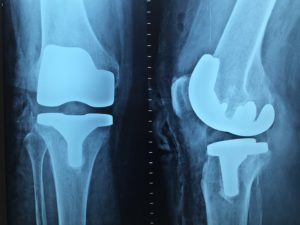

O exame chamado de radiografia libera um tipo de luz especial, os chamados raio-x que acabam sendo absorvidas pela parte do corpo que está exposta à essa luz e sendo capturada em um tipo especial de filme, que revela o local onde esses raios foram absorvidos1.

Os exames de raio X são comumente usados para analisar fraturas em diversas partes do corpo, pois com ele, os ossos são facilmente capturados e é possível ver com precisão se há alguma anomalia. Em alguns órgãos como o pulmão, por exemplo, também é possível identificar se há alguma anomalia ou doença através desse tipo de exame.